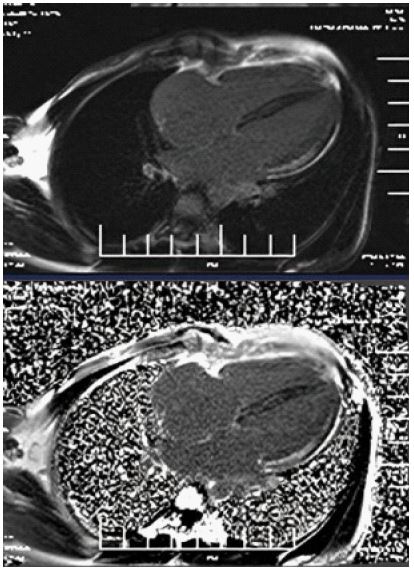

A 33-year-old female with no prior comorbidities presented with a seven-day history of high-grade fever, chills, rigors, dyspnea, and cough with borderline blood pressure requiring inotropes. Preliminary evaluation with ECG revealed sinus tachycardia and a 2D echo revealed global LV hypokinesia and severe Left ventricular dysfunction with LVEF of 30%. Initial laboratory investigations revealed elevated troponin with elevated NT-Pro-BNP suggestive of myocardial injury and acute heart failure, anemia (Hb: 9 g/dL), and elevated TSH (7.8 mIU/L), and mild renal dysfunction. The patient was admitted to the Intensive Care Unit and was treated for Heart Failure. A cardiac MRI was done, and it showed significant mid-myocardial Late Gadolinium Enhancement (LGE) in the LV free wall, sparing the endocardium and epicardium. While mid-myocardial LGE is commonly associated with myocarditis, it can also be seen in other conditions such as sarcoidosis, dilated cardiomyopathy, and Anderson Fabry disease. In this case, the findings were interpreted in conjunction with the clinical presentation, including recent febrile illness, elevated troponin, and rapid LV dysfunction. The imaging met the revised Lake Louise Criteria, supporting a diagnosis of probable myocarditis (Figures 1-3). Patient was started on IV Methylprednisolone 1 g daily for three days and then started on Oral prednisolone 1 mg/kg/day. Four days into her illness, she experienced two syncopal episodes and was found to have bradycardia with a heart rate of 30/min. An ECG revealed a complete heart block (Figure 4) with a wide-complex escape rhythm, and rising troponin levels indicated myocardial injury. A transvenous temporary pacemaker was placed, stabilizing her initially. A formal Transthoracic Echocardiogram (TTE) was performed after temporary pacemaker placement, which revealed the same moderate to severe LV dysfunction and no additional complications. Sarcoidosis was considered due to mildly elevated ACE levels (61 U/L), but further testing, including CT chest, EBUS, and node biopsy, was not feasible due to the patient’s rapid deterioration. Giant cell myocarditis, though rare in young patients, was also considered, given the aggressive course and refractory ventricular arrhythmias. A comprehensive evaluation could not be conducted due to the rapid progression of the disease. However, viral myocarditis remained the most likely etiology based on clinical presentation, negative H1N1 swab, and absence of autoimmune markers (ANA: 1:40, dsDNA < 30 IU/mL) (Table 1). After TPI, she developed slow ventricular tachycardia (130/min) (Figure 5), which persisted despite multiple attempts at overdrive pacing. Amiodarone was initiated (150 mg IV bolus, followed by 1 mg/min for 6 hours, then 0.5 mg/min for 18 hours), but VT remained refractory. Lidocaine (1.5 mg/kg IV bolus, followed by 1 mg/min infusion) was added, but the arrhythmia remained refractory. Overdrive pacing was attempted but was discontinued after the onset of Polymorphic Ventricular Tachycardia (PMVT). Given the fulminant nature of myocarditis, catheter ablation was not attempted, as the arrhythmogenic substrate was likely diffuse rather than focal, reducing the likelihood of procedural success. The patient continued to deteriorate into refractory cardiogenic shock despite maximal inotropic and antiarrhythmic therapy. She experienced cardiac arrest and could not be resuscitated. Referral for mechanical circulatory support (ECMO) was considered, but stabilization for transfer was not possible given the rapid decline. Post-mortem biopsy was not performed due to lack of consent.

Figure 2: Four chamber view axial T2 White blood sequence shows Hyperintensity in the myocardium along the Left ventricular free wall, suggestive of Edema.

Figure 3: Upper image - 4 chamber post contrast T1 vibe sequence, Lower image - 4 chamber phase contrast T1 sequence - shows mid myocardial late gadolinium enhancement along left ventricular free wall with sparing of endo & epicardium.